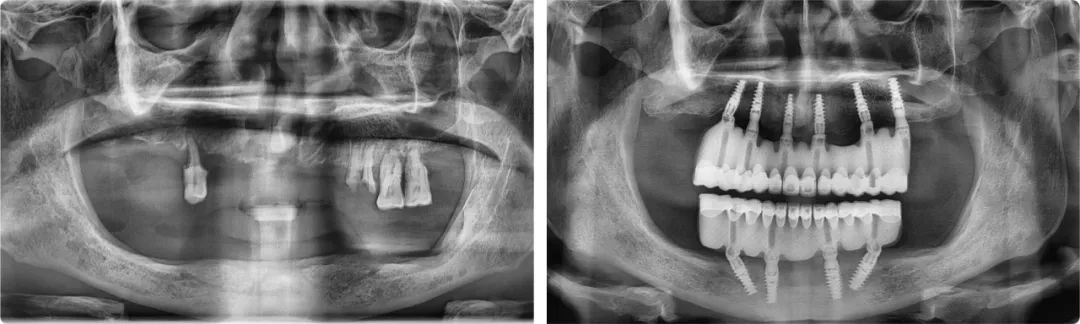

王旭东首例全口种植案例术前术后全景片

2019年12月31日,拔牙、植入10颗种植体、取模、戴牙(临时修复体)、调整,当所有治疗程序全部完成,时针已滑过零点。这次跨年手术是王旭东完成的第一例全口种植修复治疗,也是陈医生过得最开心的一个元旦。新的一年,他终于可以正常吃饭、说话,无所顾忌地大笑了。